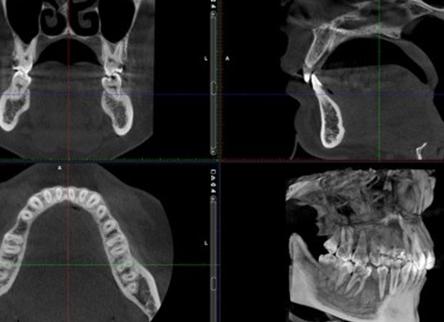

Компьютерная томография в стоматологии: опухоль верхней челюсти

КТ-диагностика помогает не только получить качественные срезы объекта, но и сформировать трехмерное изображение. Обследование проводится в реальном времени. Двухмерная картинка значительно проигрывает по качеству 3D отображению, так как на снимке визуализируется суммарное наложение множества анатомических объектов. При желании рассмотреть объект под нужным углом оборудование для компьютерной томографии позволяет исследовать предмет в определенной плоскости.

Толщина срезов устанавливается программно. На современном оборудовании можно сделать томограммы через 1 мм. При анализе рентгеновской картины специалист имеет возможность просматривать каждый уровень отдельно. Достоинством подхода является вероятность визуализации опухолей на ранней стадии. Другими методами, кроме магнитно-резонансной томографии (МРТ) нельзя определить выявить рак на ранней стадии, поэтому ученые разрабатывают возможности массовой КТ-диагностики не только в стоматологии, но и других областях медицины. Для решения этого вопроса требуется снижение лучевой нагрузки на пациента путем использования современных алгоритмов.

Конусно-лучевая компьютерная томография предполагает изготовление аксиальных снимков, на основе которых в будущем изготавливается трехмерная реконструкция.

Объектная модель используется для изготовления на основе сканов трехмерной реконструкции. Картину возможно создать не сразу после сканирования, а через некоторое время. Графические данные о сканировании сохраняются в виртуальной памяти компьютера. Из-за особенностей регистрации изображений КЛКТ получила несколько синонимов – челюстно-лицевой КТ, объемная томография.

Подход позволяет визуализировать самые мелкие патологические детали в ротовой полости – трещины зубов, свищевые ходы, добавочные ветвления корня. Трехмерная реконструкция позволяет изучить корень зуба в трех плоскостях – мезиодистальная, вестибулярная, вертикальная.